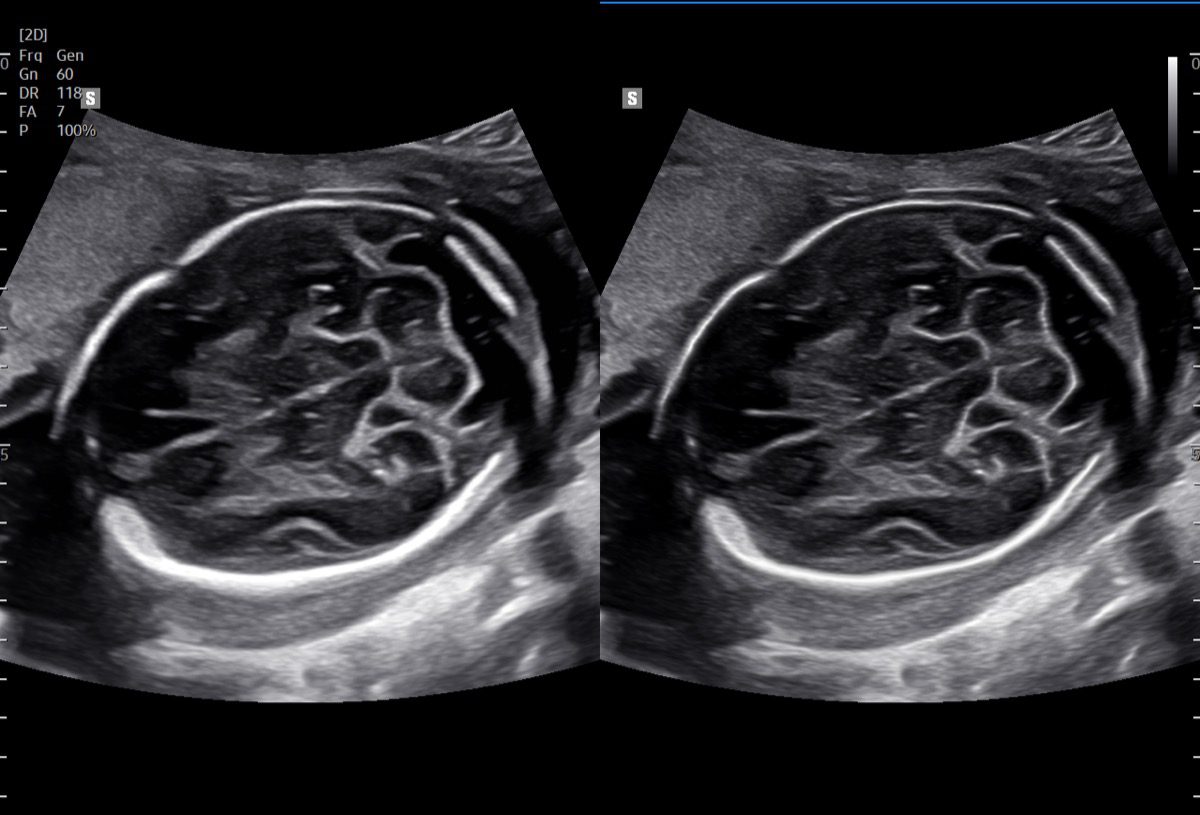

Comprehensive, advanced and expert MFM care for high-risk pregnancies

- Fetal anomalies